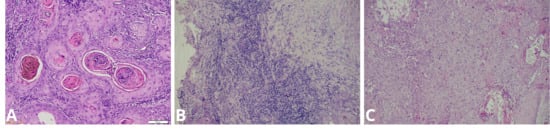

Epstein–Barr Virus Infection Is Associated with an Elevated Tumor–Stroma Ratio and Older Age in Oral Squamous Cell Carcinoma

by Eris Nurul Rahmadhini, Irna Sufiawati, Hasrayati Agustina, Okky Husain, Seto Adiantoro Sadputranto and Adi Idris

Viruses 2026, 18(2), 241; https://doi.org/10.3390/v18020241 (registering DOI) - 14 Feb 2026

Epstein–Barr virus (EBV) is an oncogenic virus implicated in several epithelial malignancies; however, its role in the tumor microenvironment of oral squamous cell carcinoma (OSCC) remains unclear. This study investigated the association between EBV infection and clinicopathological and microenvironmental features of OSCC. A cross-sectional analysis was conducted on 62 archived OSCC biopsy specimens. EBV was detected using polymerase chain reaction (PCR), and clinical data were obtained from medical records. Tumor–stroma ratio (TSR), perineural invasion (PNI), lymphovascular invasion (LVI), and histological differentiation were assessed microscopically, while tumor-infiltrating lymphocytes (TILs) were quantified using ImageJ software version 1.54j (National Institutes of Health, Bethesda, MD, USA). EBV DNA was identified in 43.5% of cases. EBV positivity was significantly associated with older age (p = 0.046), especially among patients aged 60 years or older. All EBV-positive tumors exhibited a high tumor–stroma ratio, which was significantly associated with EBV status (p = 0.031). No significant associations were observed between EBV status and sex, tumor site, clinical stage, TILs, PNI, LVI, or histological differentiation. These findings indicate that EBV-positive OSCC is characterized by distinct microenvironmental features, particularly an elevated tumor–stroma ratio, and suggest a potential role for EBV status in microenvironmental profiling and prognostic stratification. Full article